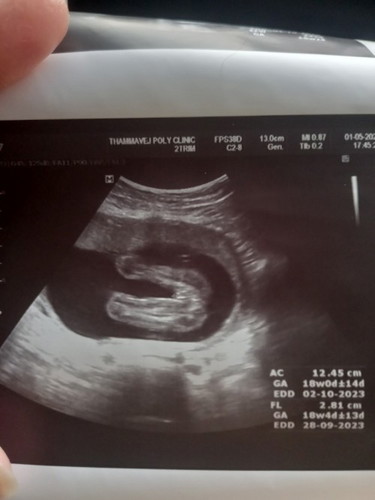

อยากสอบถามแม่ๆที่มีประสบการณ์ได้ลูกสาว ช่วยดูใบซาวด์ให้หน่อยค่ะว่าได้ลูกสาวจริงมั้ยคะ หมอบอกได้ลูกสาว แต่บางคนทักว่าเหมือนจู๋ แม่แอบกังวลค่ะ ท้องสองอยากได้ลูกสาว

ลูกสาวแน่ ๆค่ะ ซูมดูเห็นเป็นลูกศร ไม่ใช่จู๋

ใช่ค่ะแม่ปลายแหลมๆเป็นลูกศร 🥰

ดูเหมือนจู๋จริงแม่ มีแหลมๆออกมา😅

ที่แหลมๆเป็นปลายลูกศรที่หมอชี้ค่ะแม่ รอสิ้นเดือนไปซาวด์ดูเพศอีกรอบ ลุ้นสุดๆ 😅